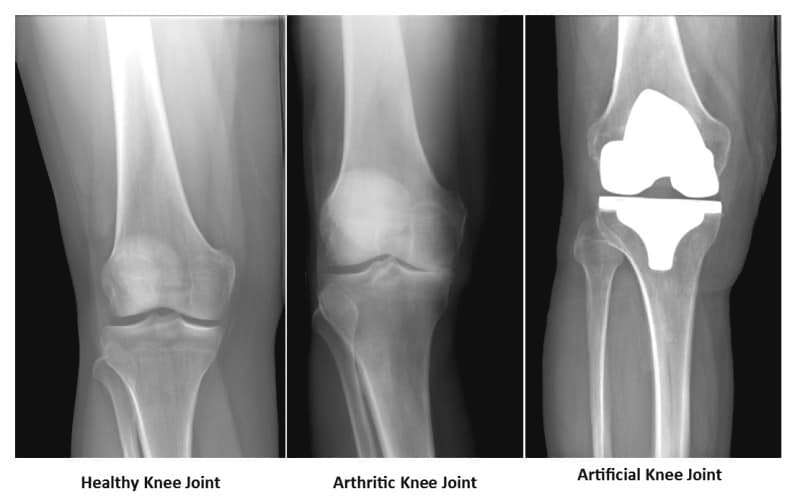

撰文:呂瑜軒物理治療師(Ms. Chantal Lu)特別鳴謝:蕭女士作運動示範膝關節置換手術,俗稱換骹,是指將嚴重磨損及退化的膝關節部分切除,再換上人工關節。手術通常用於嚴重關節炎患者,通常患者在經過一段時間的保守治療之後,疼痛及功能都不見改善,經骨科醫生評估後,便可考慮進行膝關節換置手術。膝關節換置手術分為全膝關節置換及半膝關節置換。半膝關節置換恢復時間快,術後的活動限制小,若膝關節只是半側磨損(通常為內側),整體膝關節尚維持正常活動幅度,則可考慮半膝關節置換。而全膝關節置換則是將磨損的股骨及脛骨關節表面切除後,安裝由合金及塑膠組成的人工關節,重建膝關節的功能及活動幅度。現今所採用的人工關節物料非常堅固,置換後膝關節可使用長達15~20年。全膝關節置換術是一項常見且成熟的手術,但仍會有一般手術的併發症,例如感染及靜脈栓塞,提早開始活動有助於避免靜脈血栓的形成。手術後的復康手術後及時接受物理治療至關重要,物理治療師會指導病人進行膝關節活動度、腿部肌力強化訓練、運動功能及神經肌肉再訓練等,令患者盡早恢復步行及日常活動能力,進而提升人工膝關節活動的質素及使用壽命。一般而言,膝關節置換手術後的第一天即可下床站立及行走,患者便可以開始進行物理治療,此時的物理治療會著重術後的關節腫脹以及疼痛控制,並教導患者上下床、起身坐下以及使用柺杖行走的正確方式。隨著術後傷口的恢復,物理治療師會因應病人嘅進展,再增加訓練的強度,使新關節能更輕鬆應付生活的不同難度及挑戰,例如上落樓梯、斜路。手術後的膝關節前側會有7~8吋的傷口,周圍可能會有些麻痺,造成麻痺的原因是表皮神經受損,約一年後會逐漸改善。新關節初時可能感到些許僵硬 ,特別是彎曲的時候,隨著傷口癒合及物理治療的協助,這些問題便能逐漸減少,使患者重拾活動能力。一般而言,患者通常在手術後接受三到六週的復康治療及家居運動的訓練後,絕大部分均可如常行走及進行日常活動,然而膝關節置換手術雖能明顯減少疼痛,大幅改善患者日常活動能力,但一些高衝擊的活動,例如跑步和跳躍還是要盡量避免或減少,以降低人工關節的損耗。以下是膝關節置換手術後初期的重要復康運動,可在家中練習,如運動進行的過程中感覺不適或疼痛增加,建議大家先暫停並盡早求醫及諮詢物理治療師意見。

圖左:健康的膝關節

圖中:已退化的膝關節

圖右:置換後的膝關節手術後約6週恢復良好的傷口